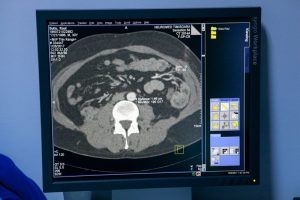

Cea de-a două premieră se referă la o intervenţie endovasculara la nivelul arterei iliace.Localizarea este deosebit de gravă, ruptură acestui anevrism putând duce chiar şi la deces. Tratamentul s-a realizat prin implantarea pentru prima oară în ţară noastră a unei proteze special construite pentru arteră iliacă.

“Celălalt pacient este un caz foarte, foarte dificil, este un tânăr cu o boală severă generală, care a făcut să aibe mai multe dilatatii arteriale în interiorul corpului, pentru care s-a intervenit de mai multe ori, inclusiv în abdomen sau în diverse alte locuri din corp. Din cauza fragilităţii extreme a vaselor leziunea pe care noi am tratat-o astăzi şi care este în abdomen, nu avea indicaţie decât endovascular.”, a spus Mihai Ionac, şeful Clinicii de Chirurgie Vasculară.

“Este un mare avantaj pentru pacient. Nu mai trebuie tăiat abdomenul având un risc ridicat de infectare, acum se poate face printr-o mică incizie excluzând anevrismul. Această tehnică se foloseşte în Germania, Anglia, Franţa, Norvegia pentru mai mult de jumătate dintre pacienţi şi sper că acest lucru se va întâmplă şi aici, sper că medicii să ducă acest proiect mai departe.”, a declarat Dr. Rolf Dammrau, chirurg vascular din Germania.